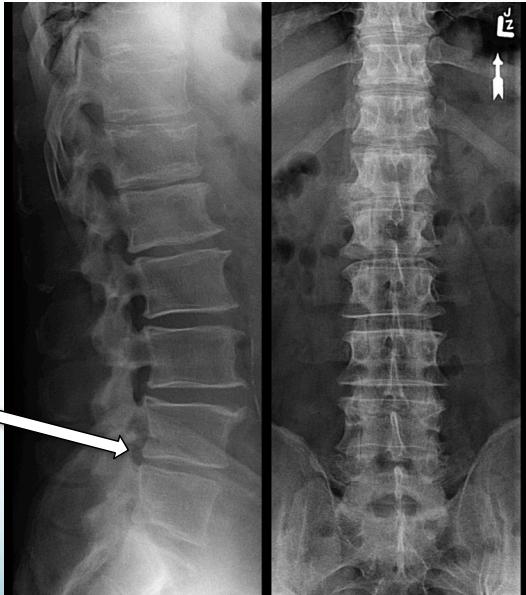

Imaging

X-Ray:

- Rules out bony pathology

- Shows narrowing of disc space

- Note: Not very helpful in chronic cases, mainly to exclude other causes like tumor, fractures, or deformity

- X-ray:

- To rule out other bony pathology

- May show disc space narrowing